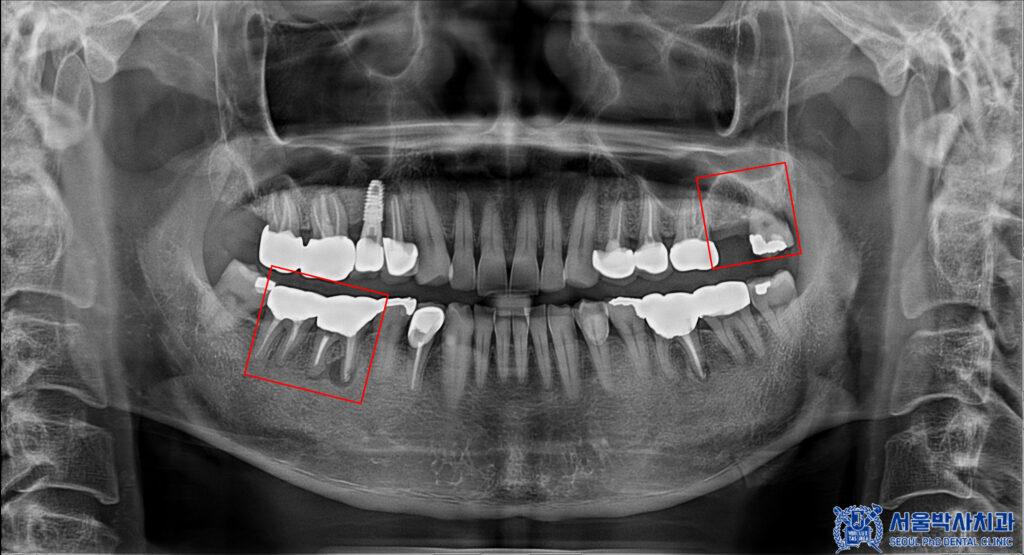

확인해 보니,

왼쪽 위 어금니의 상실이 있었고

사랑니도 있었습니다.

또한 오른쪽 아래

첫번째 큰 어금니 뿌리 끝으로

염증이 크게 잡혀있는 것을

확인 할 수 있었습니다.

CT를 촬영하여 식립 위치를 확인하며

뼈의 높이와 두께, 그리고 상악동과의 거리를

정밀하게 확인을 하였습니다.